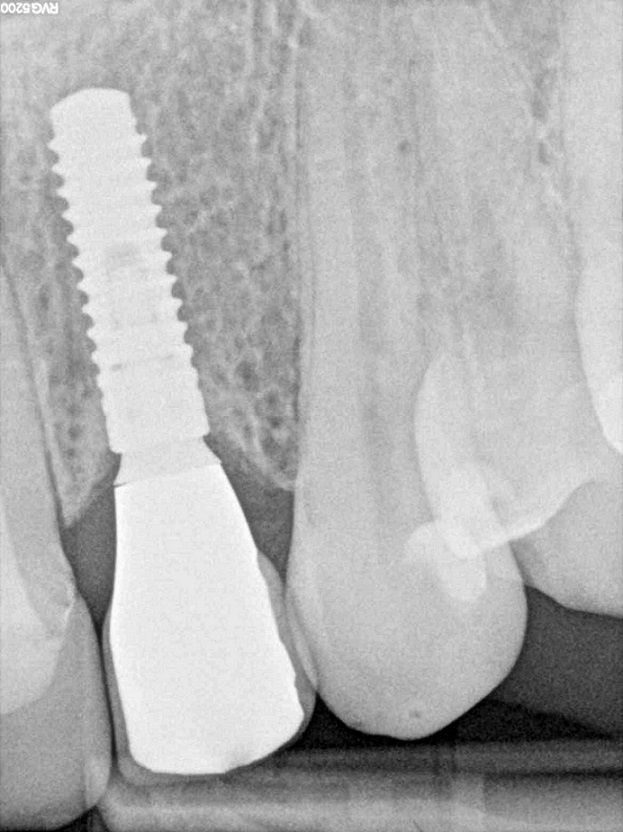

11/12 - X-ray control after 18 monthsSoft tissue thickening at immediate implant placement and GBR with mucoderm® and maxgraft® - Dr. A. Puisys